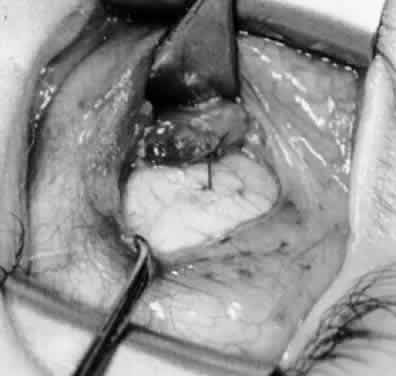

Fig. 14. The inferior temporal vortex vein, 8 mm posterior to the temporal insertion of the inferior rectus muscle, is held on a Green muscle hook.

Fig. 15. The placement of sutures within the sclera for a recession procedure of 10 mm. The anterior suture is placed 3 mm temporal and 2 mm posterior to the lateral insertion of the inferior rectus muscle, and the posterior suture is placed 3 mm further posteriorly.

Fig. 16. Two sutures straddle the inferior temporal vortex vein insertion for a 14-mm recession procedure.